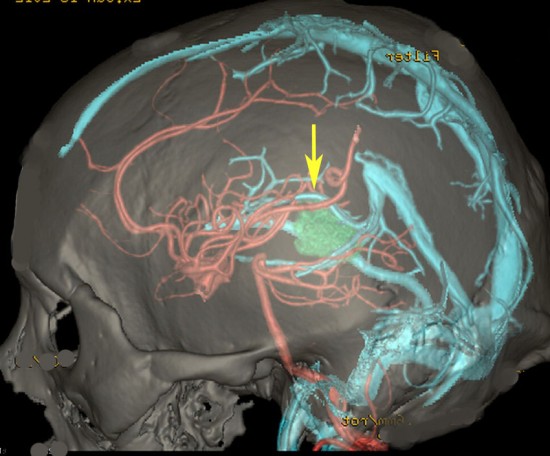

松果体周囲の静脈洞

Overview of the pineal region through the right occipital area. The occipital lobes, the falx, the tentorium, and the arachnoid membranes have been removed. BV = basal vein of Rosenthal, CV = cerebellar vermis, G = great vein of Galen, ICV = internal cerebral vein, MOV = medial occipital vein, P = pulvinar, PV = pericallosal vein, Q = quadrigeminal plate, S = splenium, SS = straight sinus, TS = transverse sinus